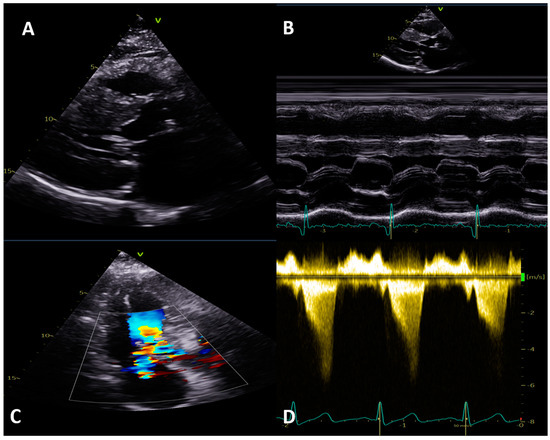

4.2. Left Ventricular Outflow Tract Obstruction

4.3. Mitral Valve Assessment